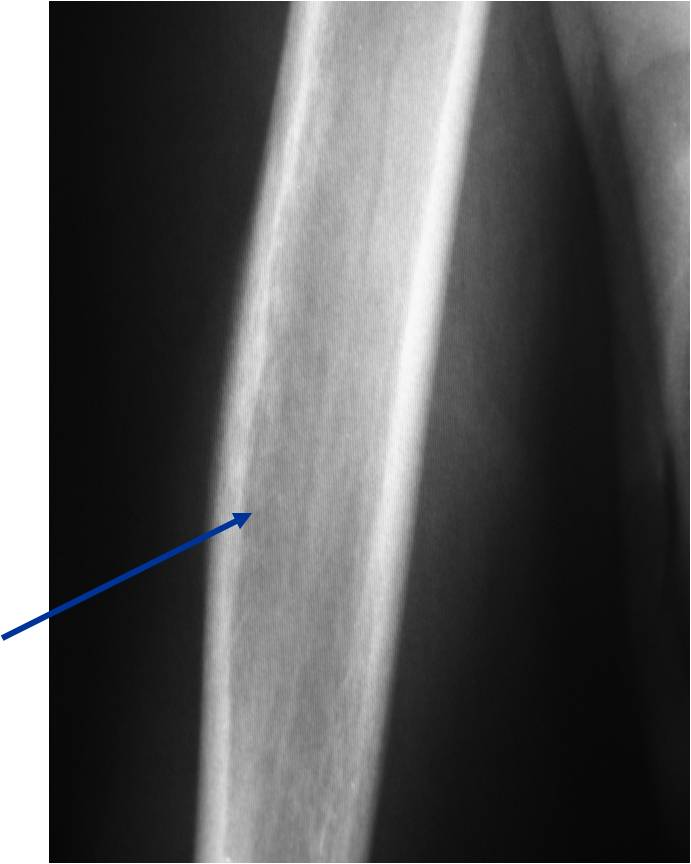

- Permeative or moth eaten bone destruction (55%)

- Metadiaphysis (75%)

- Periosteal reaction—may look benign

- Interrupted or solid single layer (66%)

Permeative/Motheaten Lesion with Pathologic Fracture